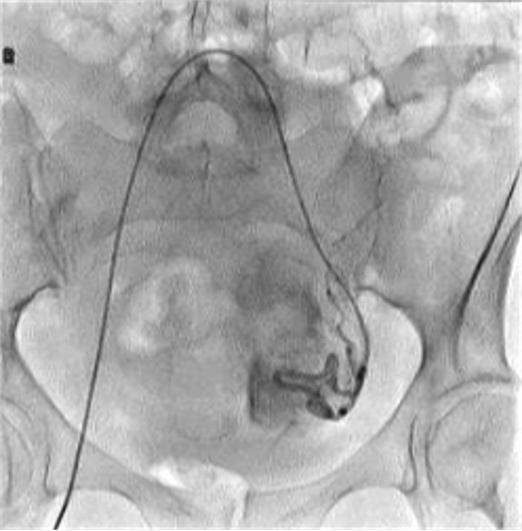

所有年龄超过 40 岁的患者, 卵巢受损 14%-43% 研究中闭经发生率(15%)与单纯UAE报告相似,可能与患者年龄(≥45岁)及卵巢储备自然下降有关。 ![]() 50岁,长期因子宫肌瘤导致月经出血过多,痛经和贫血。 子宫肌瘤栓塞术前,显示双侧子宫动脉发育不全,子宫肌瘤双侧卵巢动脉。 经皮股动脉穿刺双侧卵巢动脉栓塞,先500μm-700μm emboSphere 微球 术后4周,和6月的中短期随访,月经正常,子宫容积减少,贫血纠正,无卵巢功能衰竭。但看起来非灌注容积较少。 术后9月,由于子宫肌瘤持续存在,患者自己希望绝经,行全子宫和双侧卵巢切除术 术后病理,子宫内可见栓塞微粒伴有坏死,卵巢内也见栓塞微粒,但卵巢功能未受损。